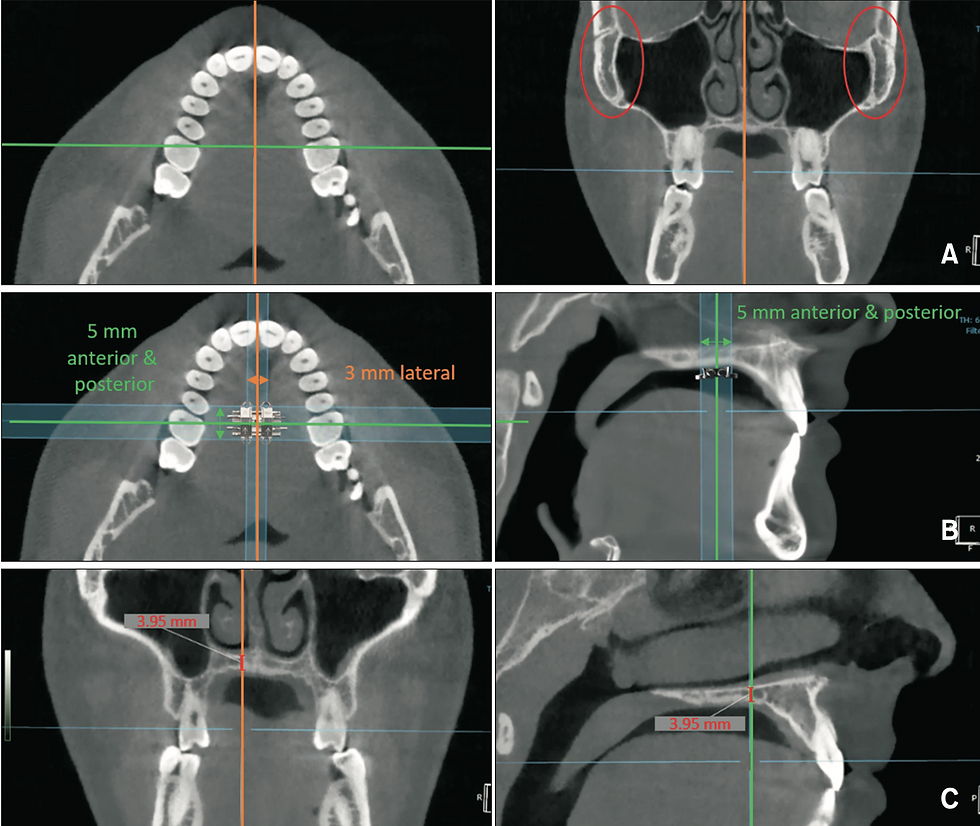

Trinta e nove participantes (12 homens e 27 mulheres; idade média, 18,2 ± 4,2 anos) foram tratados com sucesso com o aparelho MSE II. Os dados da TCFC pré e pós-expansão foram sobrepostos. Os ângulos inter-MI anteriores e posteriores pré e pós-expansão, o pescoço e a distância inter-Mi apical, o ângulo da placa, a espessura do osso palatal nas posições Mi e a abertura da sutura nas posições do MI foram medidas e comparadas.

A placa do parafuso expansor foi ligeiramente dobrada nas áreas anteriores e posteriores. Não houve diferença significativa na extensão da abertura da sutura entre o MIS anterior e posterior (p> 0,05). A linha posterior do MI ao hemi-palato foimaior que a anterior (p <0,05). A distância apical entre o MIS posteriores foram maiores que a anterior (p <0,05). A espessura palatina no MIS anteriores foi significativamente maior que a posteriormente (p> 0,01).

Os autores concluiram que no plano coronal, a angulação entre o MIS anteriores em relação à placa do parafuso do expansor foi maior do que a entre os posteriores devido à espessura do osso palatino diferencial.